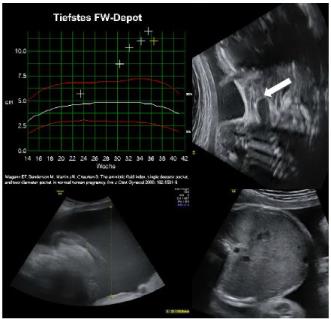

Es ist naheliegend, dass solche komplexen Mechanismen anfällig sind auf äussere Stimuli, metabolische Einflüsse sowie fetale Fehlbildungen. Störungen der Fruchtwassermenge können sich als zu viel (Polyhydramnie) oder zu wenig Fruchtwasser (Oligohydramnie) manifestieren. Die Fruchtwassermenge wird sonographisch entweder anhand des grössten Depots in vier Quadranten definiert oder als Summe von vier Messungen in den vier Quadranten. Letzterer Wert wird auch als Amniotic fluid index (AFI) bezeichnet. Ich bevorzuge die Messung des grössten Depots. Damit läuft man auch weniger Gefahr, eine Oligohydramnie zu häufig zu diagnostizieren, insbesondere am Termin. Dies wurde auch in Metaanalysen von randomisierten Studien untersucht.

Eine der auffälligsten und einfach zu erfassenden Veränderungen des Fruchtwassers ist dessen Menge. Tabelle 2 und Grafik 1 spiegeln die durchschnittliche Fruchtwassermenge in Abhängigkeit vom Gestationsalter wider.